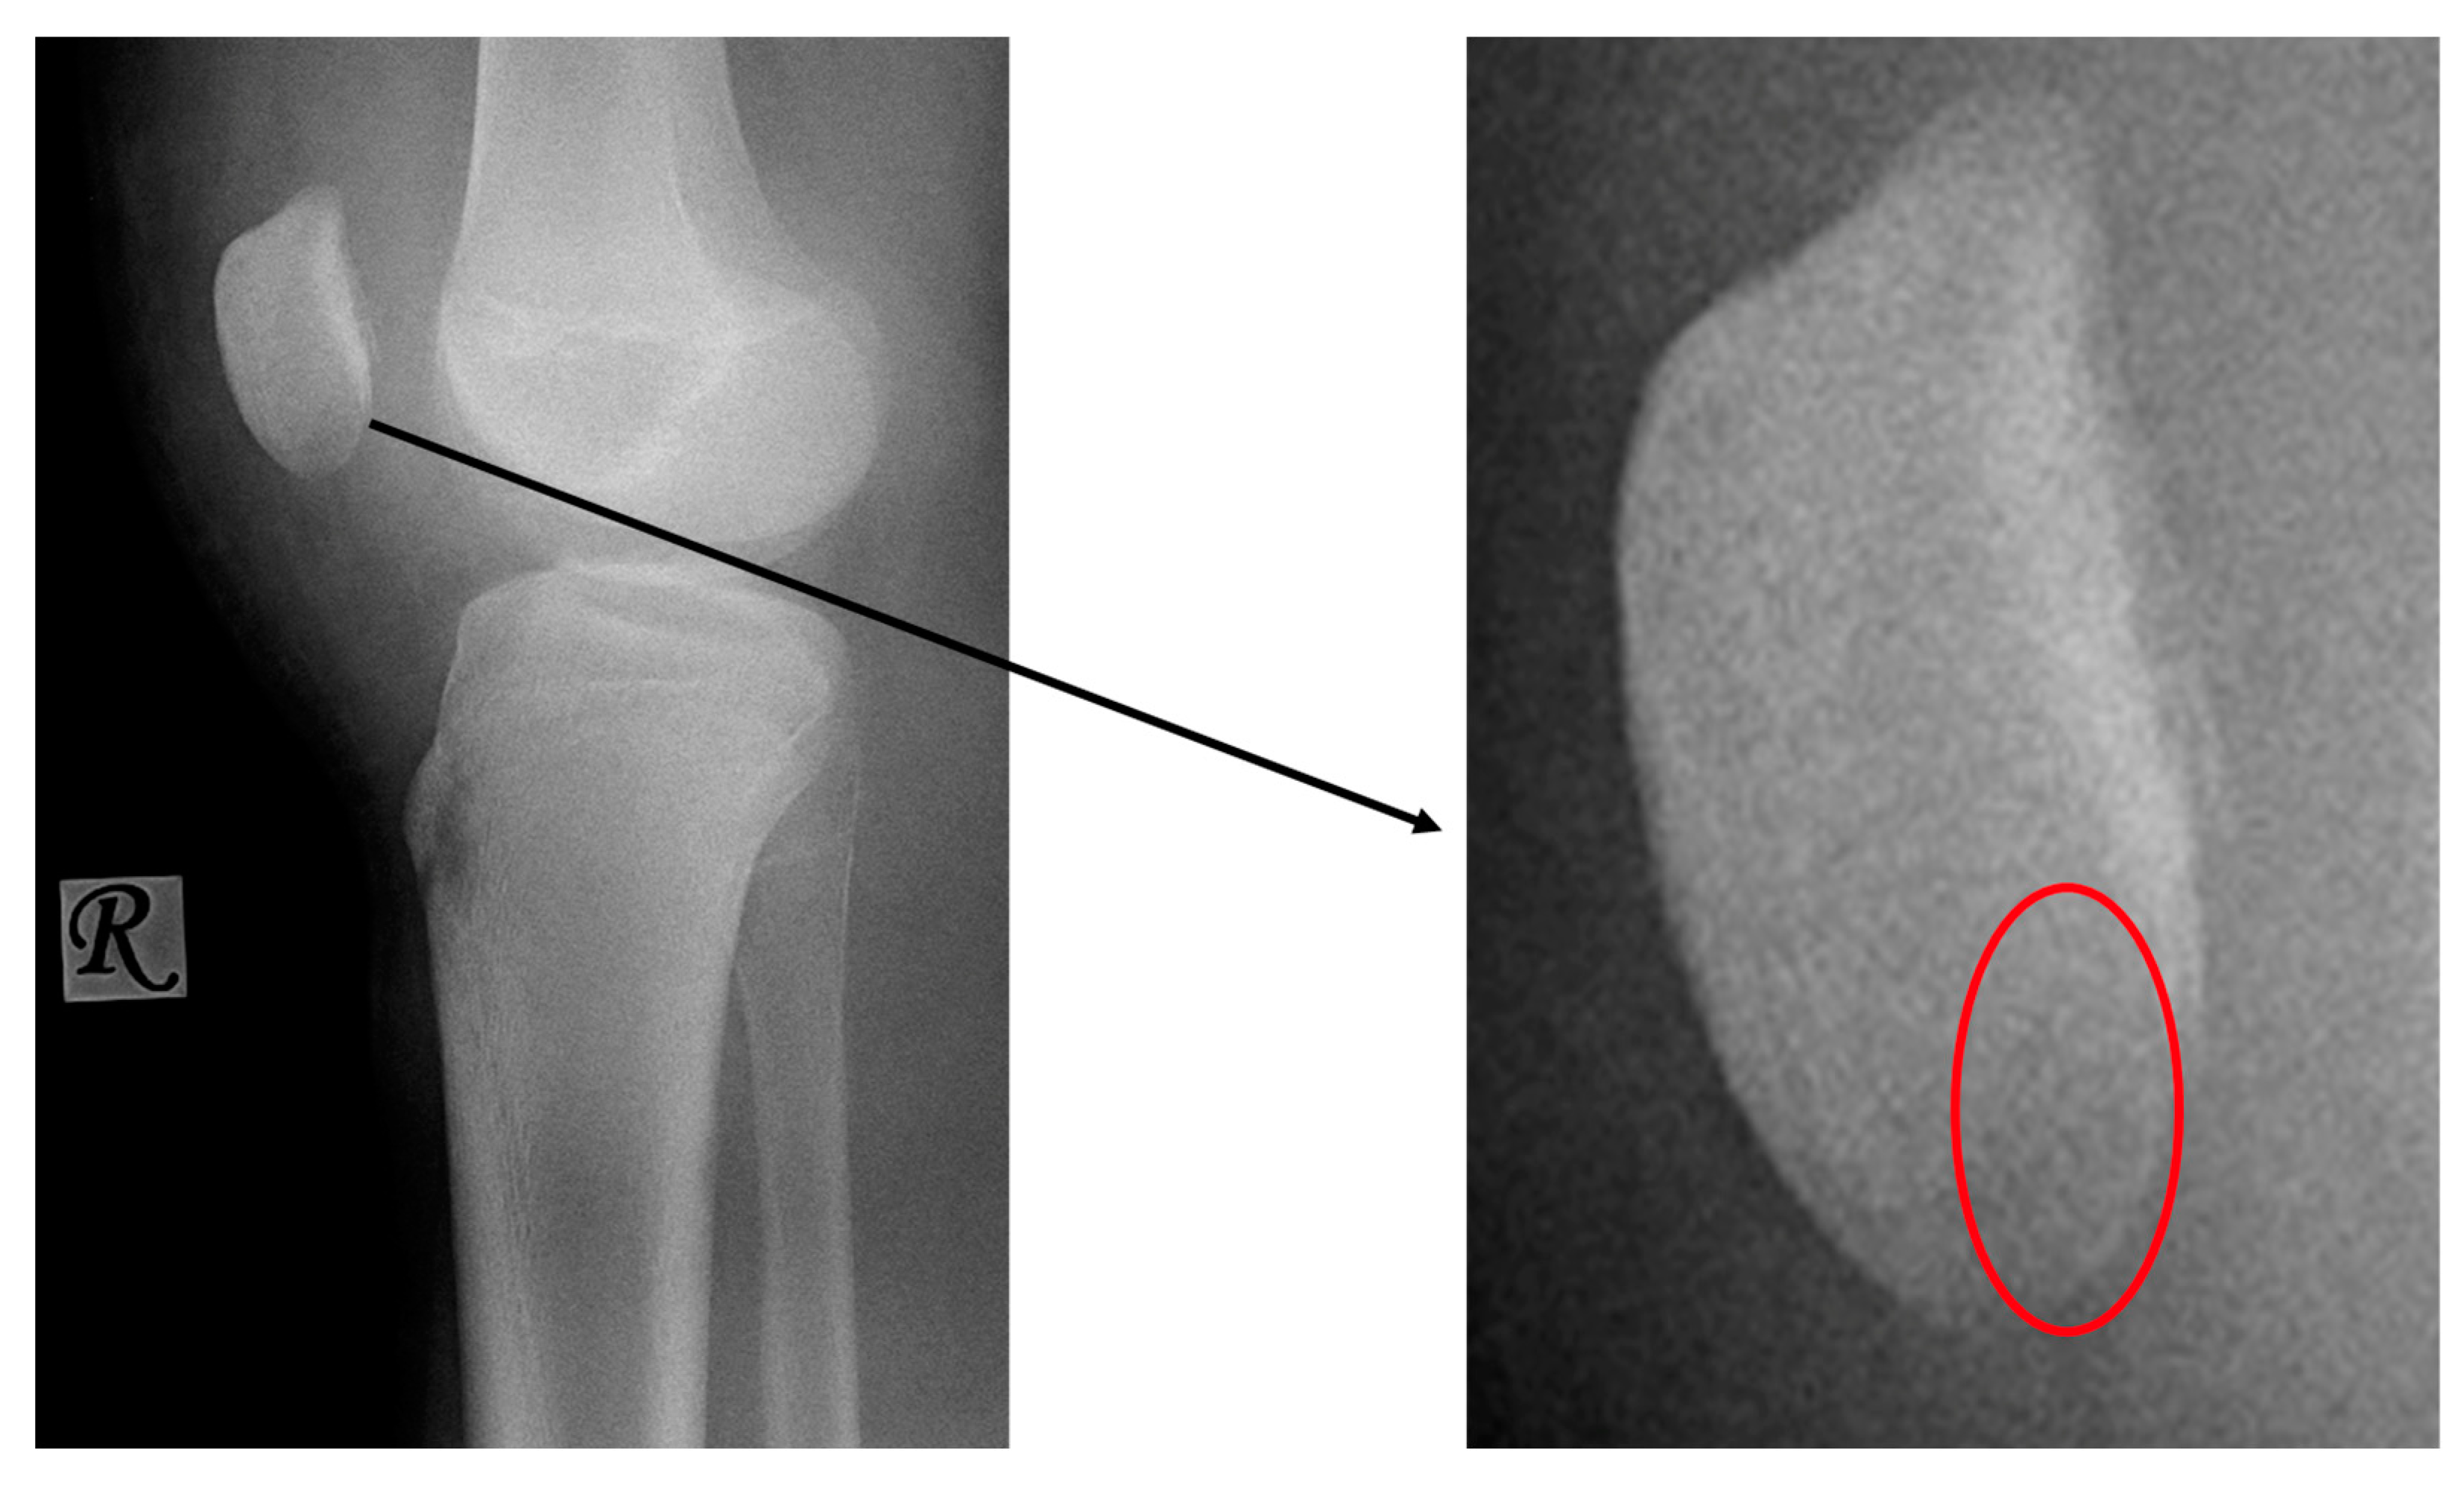

- X-ray: Negative

- X-ray: Negative or slight sclerosis

- X-ray: Lucency between fragment and normal bone.

- X-ray: Loose body, lucency